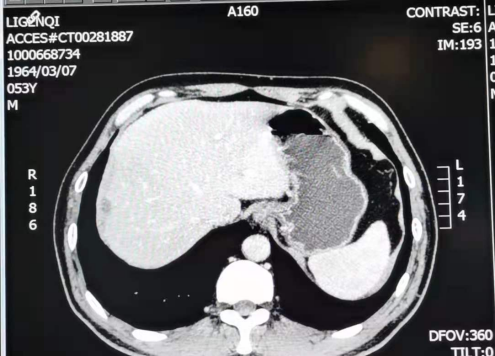

2018-01-23 CT检查示肝S8段边缘部(6-192)见一低密度结节,边界清楚,大小约1.3cm×0.8cm。

2018-07-24 复查CT

肝边缘部见多发低密度结节,边界清楚,大者约2.1cm×l.9cm,未见强化,体积较前增大,数量较前略增多;肝脏边缘结节,体积较前增大,数量较前略增多,提示腹膜种植转移。

2018-07-24 肝MRI:

1.肝S4-8段边缘处多发结节,与前片(2018-05-25)比较,部分体积较前略增大,考虑转移瘤较不典型血管瘤可能性大,建议随访;2.肝S5、S6小结节,转移待排,建议随访。